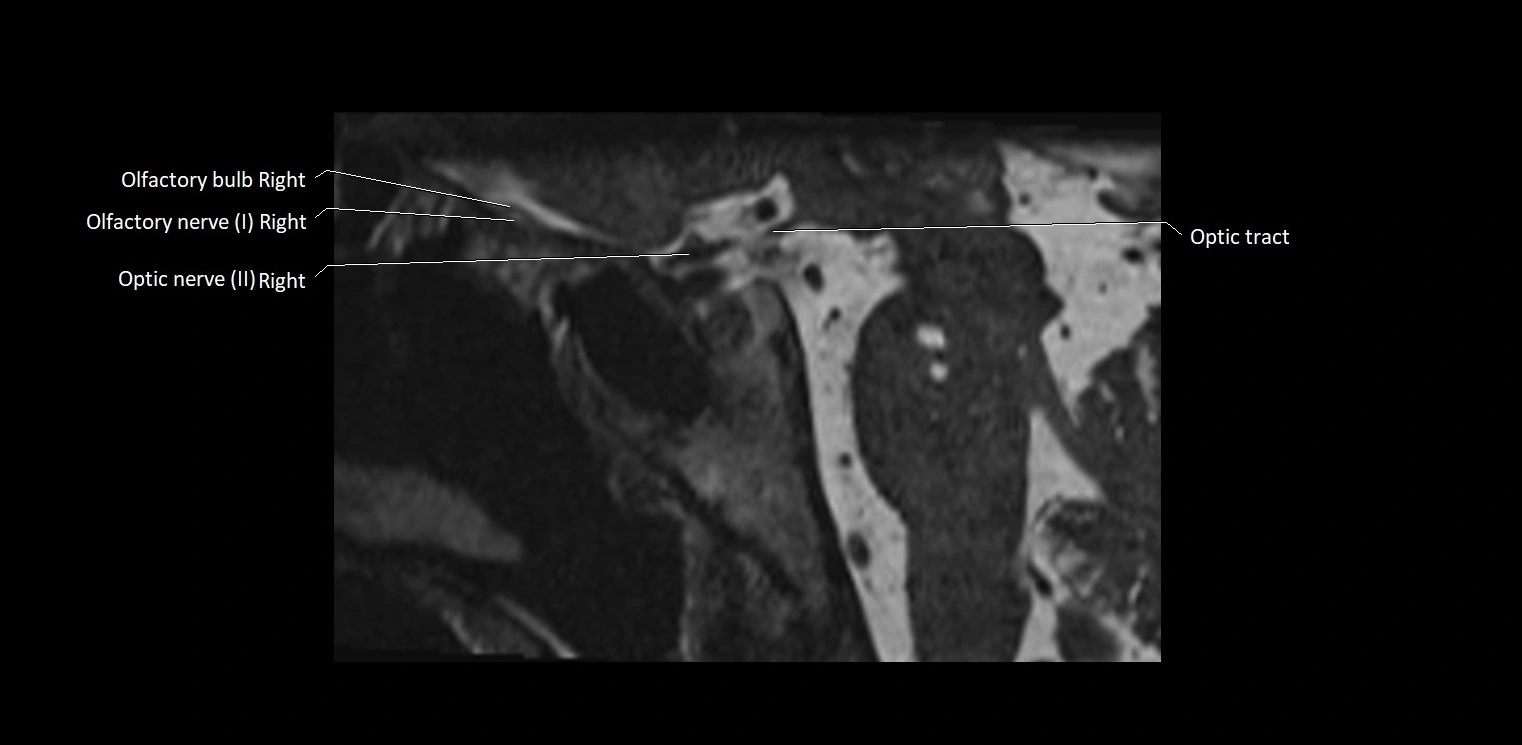

MRI Appearance

• The abducens nerve is a small, thin, linear structure

• Best visualized on high-resolution T2-weighted 3D MRI sequences (e.g., FIESTA or CISS)

• Seen as a hypointense (dark) line running from the brainstem at the pontomedullary junction, traversing the prepontine cistern, and entering Dorello’s canal under the petrosphenoidal ligament, then into the cavernous sinus, and finally the orbit

• May be challenging to visualize in standard MRI due to its small size

• Pathology may be inferred by absence, displacement, or enhancement of the nerve

MRI images

image